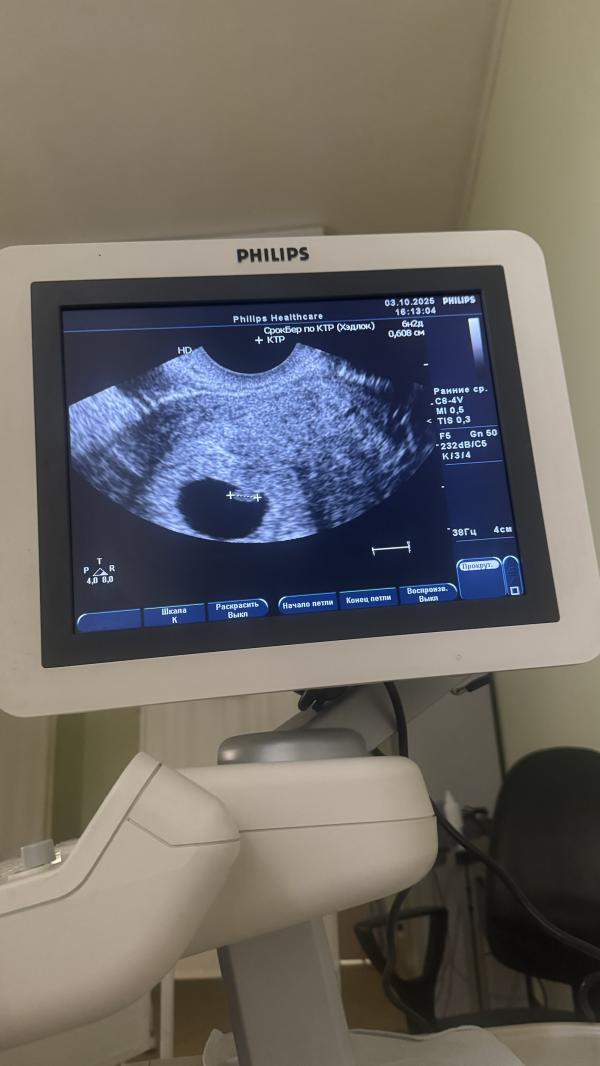

7 недель беременности: КТР 6 мм, сердцебиение есть

Срок беременности: 7.3

КТР = 6 мм

ЖМ = 5 мм

Сердцебиение есть 💓

03.10.2025